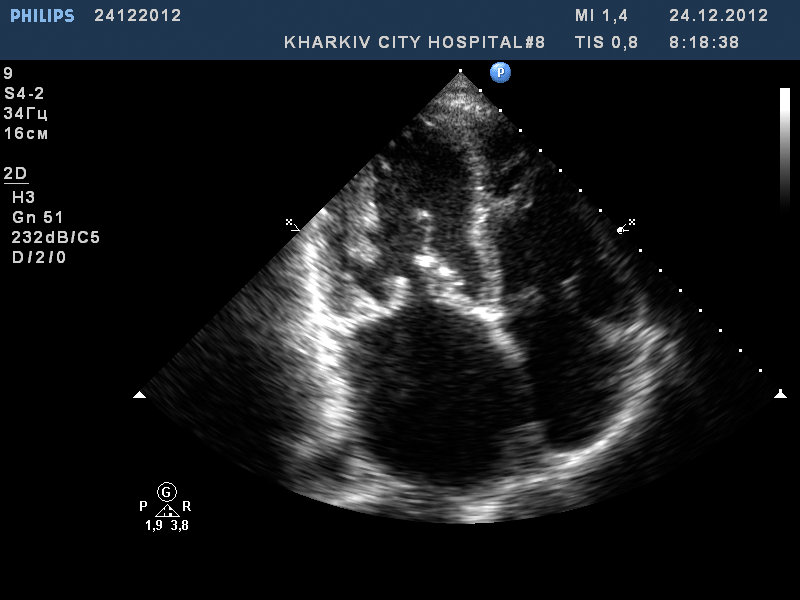

Пациент 52 лет. Поступил с нарушение ритма.

Заключение узи : склеротические изменения аорты, фиброзные изменения створок аортального клапана, незначительная недостаточность аортального клапана, частичный отрыв хорд передней створки митрального клапана, значительный митральный стеноз, умеренная МН, дилатация левого предсердия (6,0см), гипертрофия левого желудочка.